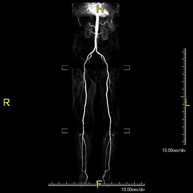

- Angio RM Arterial extremidades inferiores

Prueba diagnóstica no invasiva que consiste en el estudio vascular del sector aorto-ilíaco y de los vasos arteriales de ambas extremidades inferiores, obteniendo imágenes de alta definición anatómica mediante el empleo de un campo electromagnético y ondas de radio (con un emisor y un receptor). Es indispensable el uso de contraste paramagnético (Gadolinio). Sin embargo, no utiliza radiación ionizante. La calidad de las imágenes permite realizar reconstrucciones en 2D y 3D. Está especialmente indicado en aquellos pacientes en los que hay sospecha de enfermedad vascular de ambas extremidades, en pacientes con enfermedad vascular de ambas extremidades como el mapa vascular antes del tratamiento (percutáneo o quirúrgico), como el mapa vascular pre-quirúrgico en pacientes con lesiones óseas o musculares que requieran cirugía, etc.

- Angio-RM Arterial extremidades inferiores

Prueba diagnóstica no invasiva que consiste en el estudio de la arteria aorta abdominal, obteniendo imágenes de alta definición anatómica mediante el empleo de un campo electromagnético y ondas de radio (con un emisor y un receptor). Es indispensable el uso de contraste intravenoso paramagnético (gadolinio). Sin embargo, no utiliza radiación ionizante. La calidad de las imágenes permite realizar reconstrucciones en 2D y 3D. Está especialmente indicado en aquellos pacientes en los que hay sospecha de enfermedad vascular de ambas extremidades, en pacientes con enfermedad vascular de ambas extremidades como mapa vascular antes del tratamiento (percutáneo o quirúrgico), como mapa vascular pre-quirúrgico en pacientes con lesiones óseas o musculares que requieran cirugía…